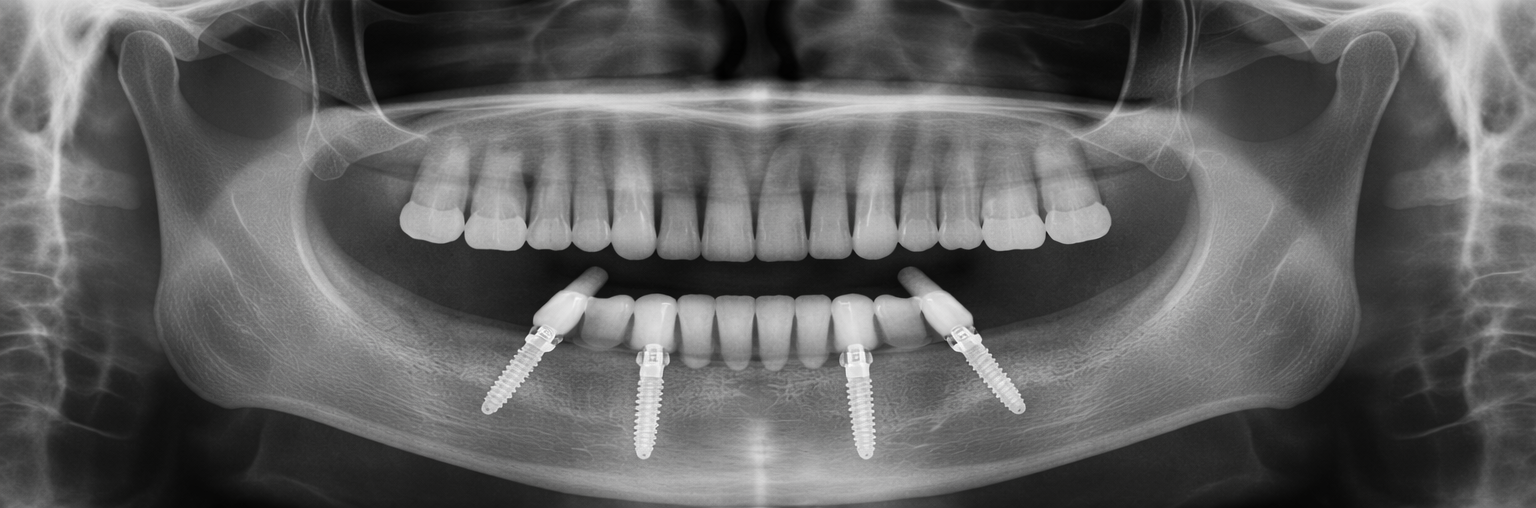

Önce & Sonra

Gerçek hasta sonuçları – sürükleyerek karşılaştırın

All on Four

Önce Önce

Sonra Sonra

Sürükleyin

İmplant Tedavisi